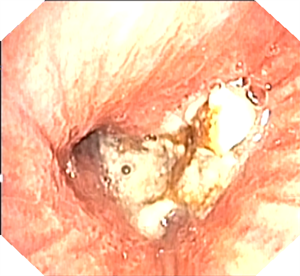

一位80岁的脑梗死、老年痴呆患者,多次在神经内科就诊,反复出现右下肺炎症伴肺不张,且伴有发热,病情不断加重。在我院呼吸科会诊后,细心的医生从老人胸部 CT 影像中发现关键问题——可疑支气管异物!为进一步明确,呼吸科医生为患者进行支气管镜检查,果然在其右下叶支气管内发现一枚动物骨头异物,并顺利取出,同时吸除大量堵塞支气管的脓液,患者肺部炎症得到有效控制。